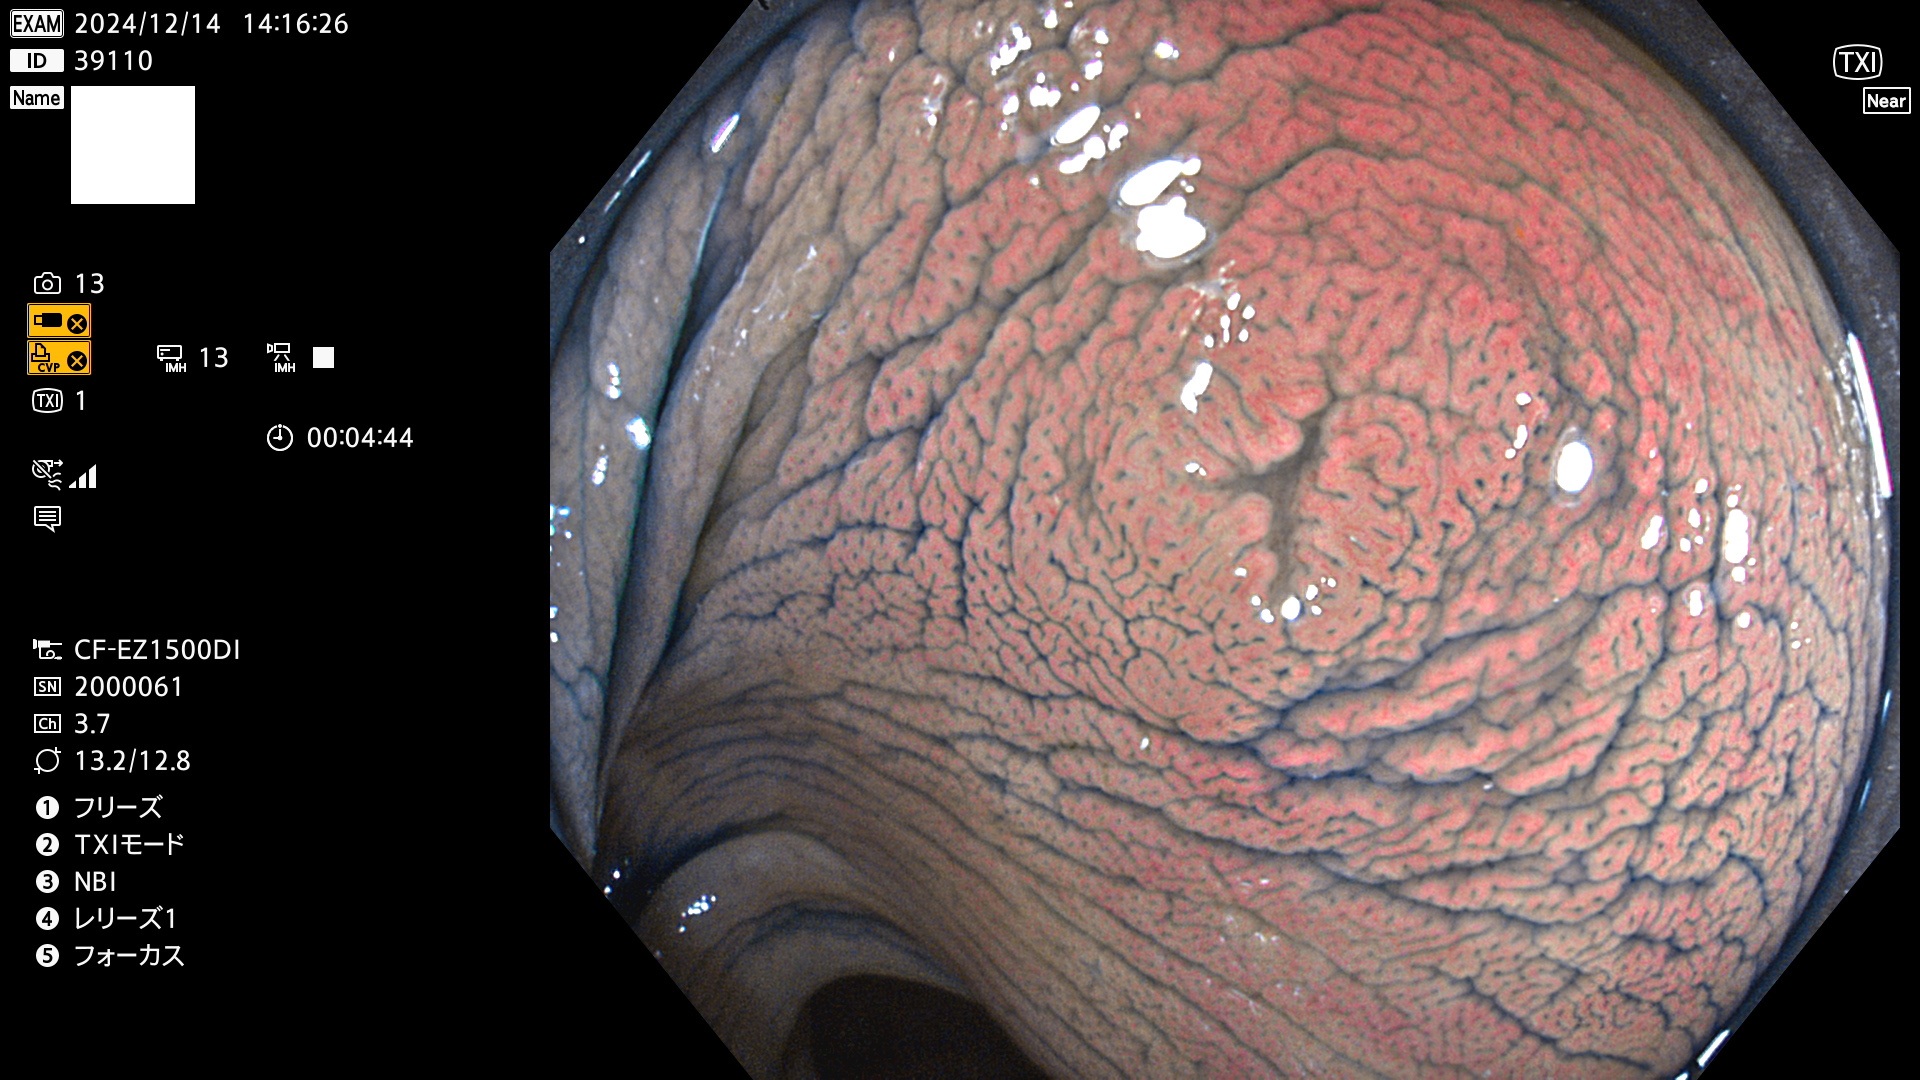

完全に平坦な物をUb、陥凹している物をUcと呼びます。最も発見が難しく危険な病変です。

専門的)Uc=De Novo癌? 内視鏡の解像度が低かった時代、このような説もありました。しかし今日の高精度内視鏡では良性の微小なUc型腺腫が日常的に見つかります。私見ですが「Ucこそが多段階発癌(Adenoma-Carcinoma Sequence)のMain Route」と考えます。

毎週の検査(木・金・土・日)に発見されたUb、Uc型・腺腫を、その週の日曜の夜にUPし1週間、提示します。

抽出の対象期間 2024年12月12日〜12月16日の5日間(60件の検査)13件 (13/60=21%)